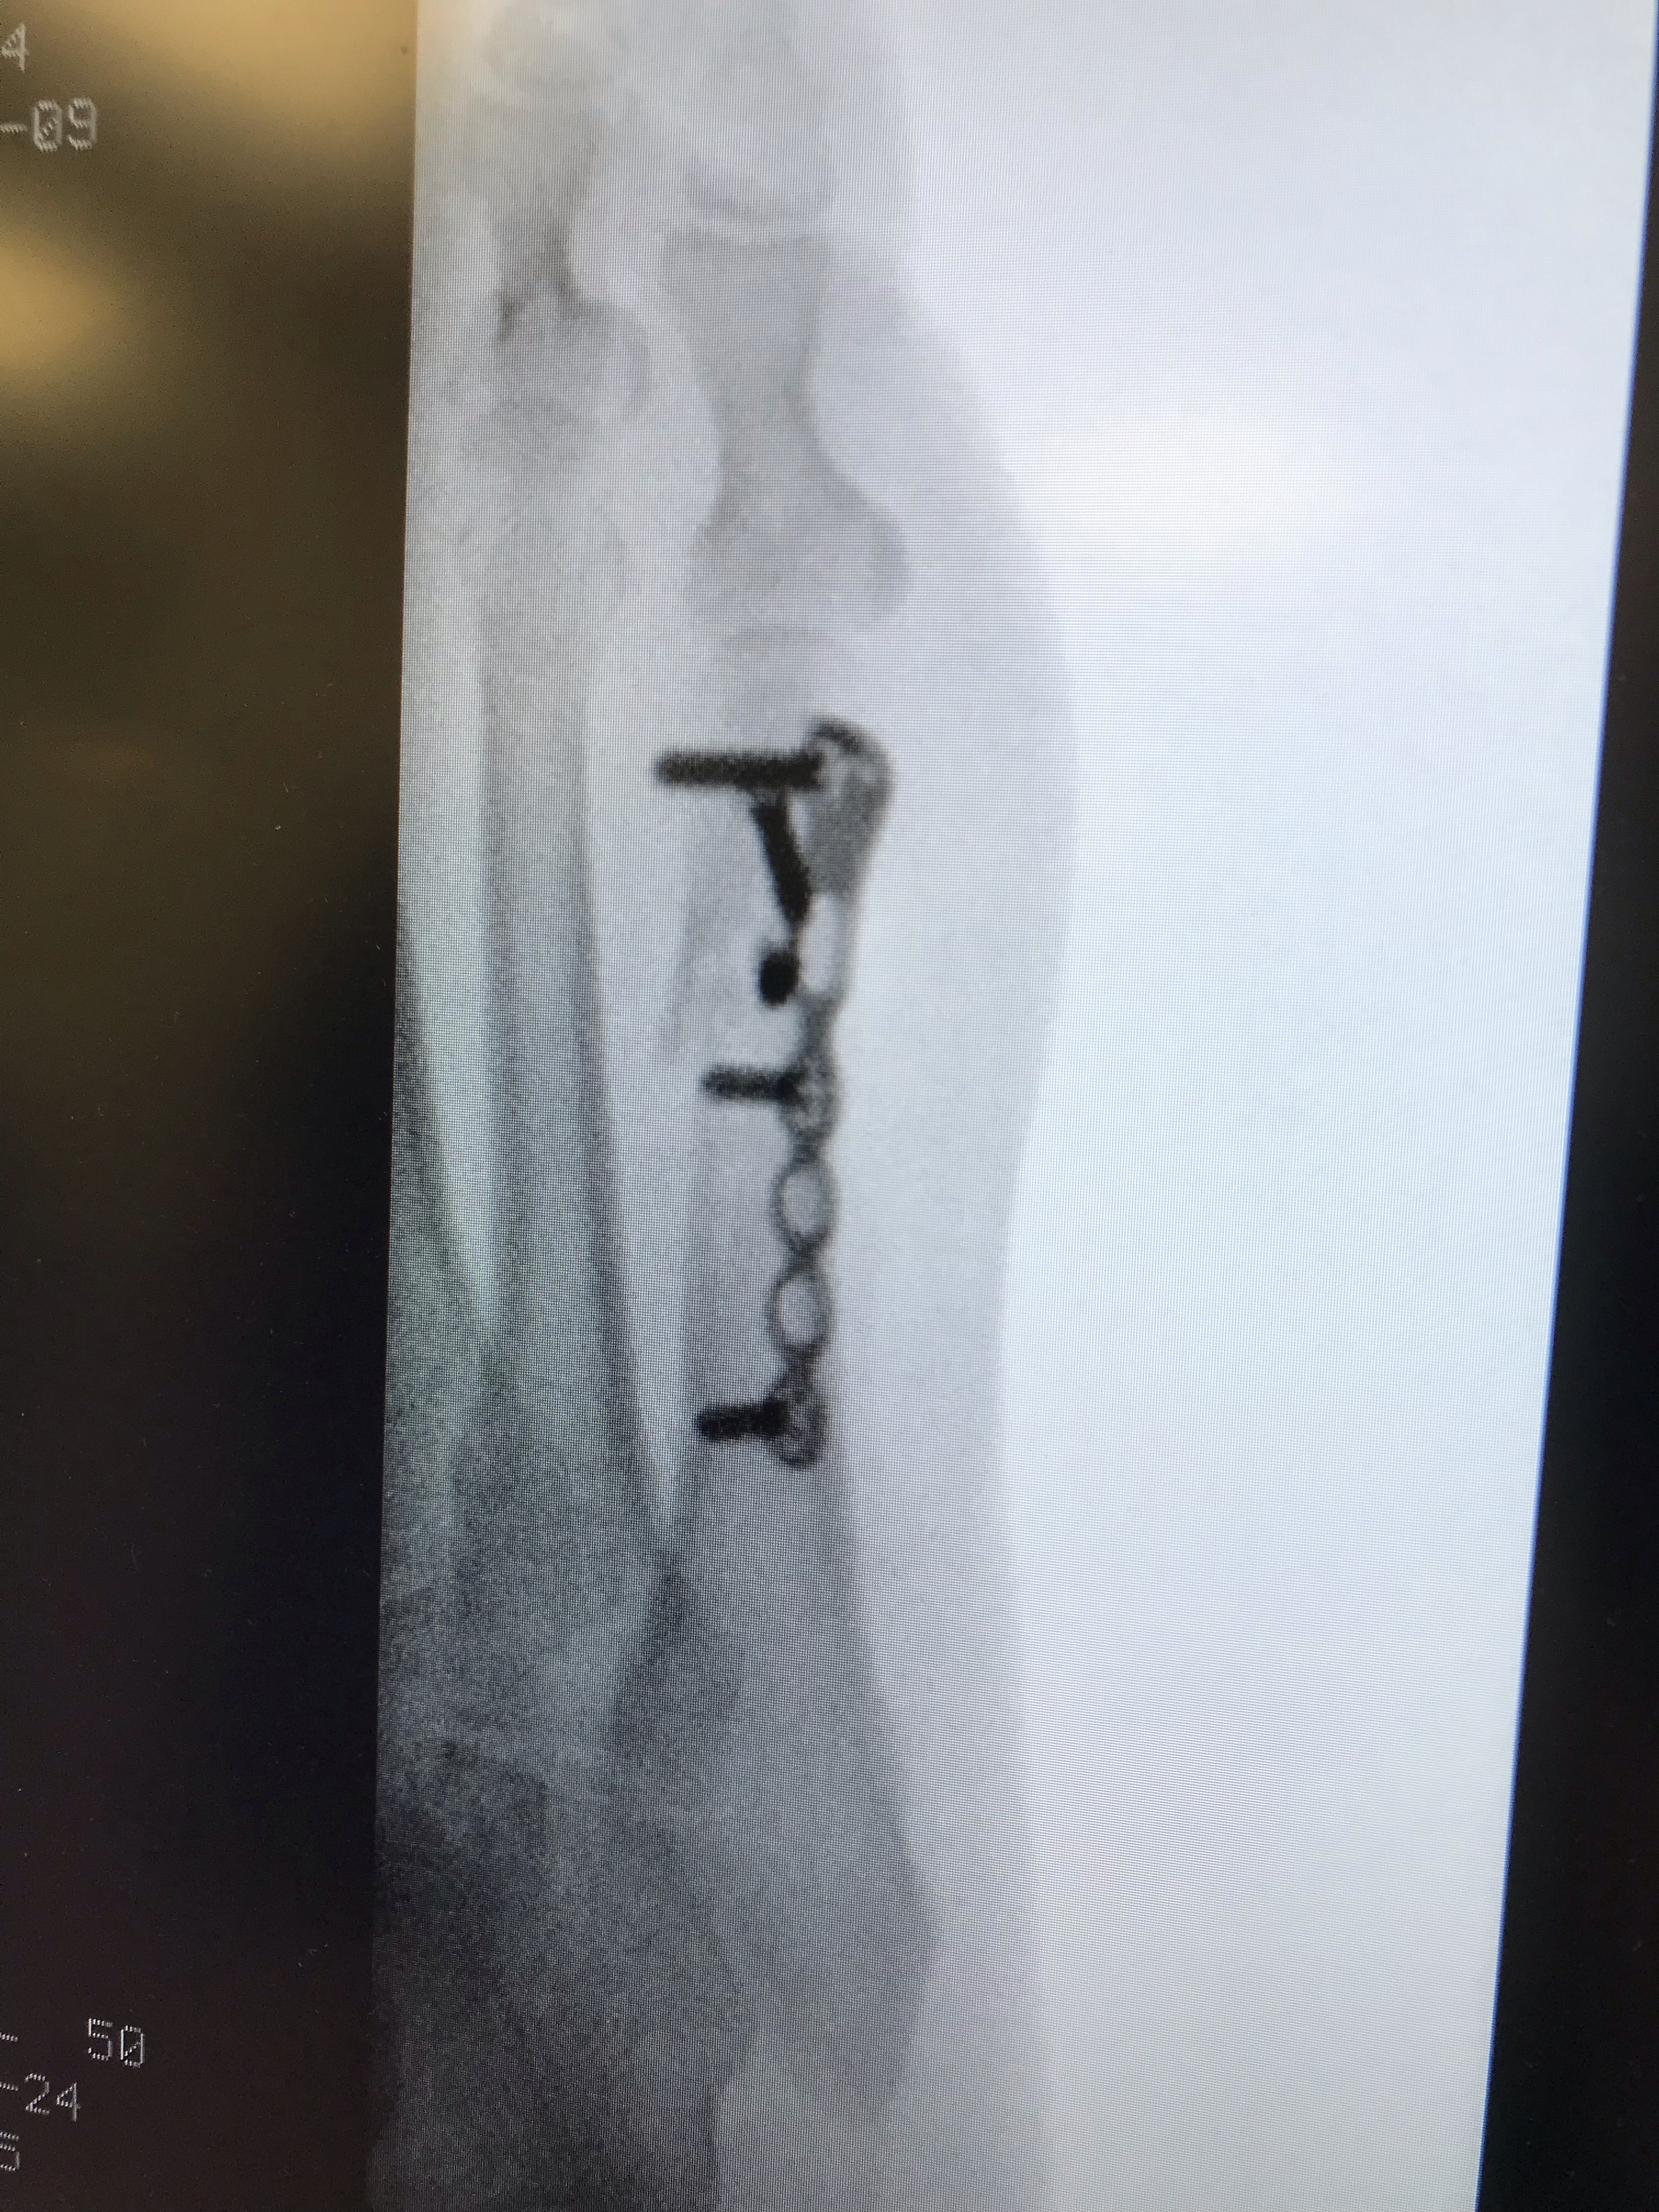

Die voetbreuk van mij had nogal wat voeten in de aarde.

Ik had er een hard hoofd in dat het op een natuurlijke manier zou genezen, de dokters hielden voet bij stuk dat het moest kunnen. Maar ik zat ermee en had een tenenkrommend lange tijd geduld. Uiteindelijk werden er spijkers met koppen geslagen. In mijn voet. Want die moest toch een handje geholpen worden. Hals over kop, op de dag voor kerst.

De orthopedisch chirurg stak de handen uit de mouwen en haalde zo bij mij een wit voetje. Want daarna nam de genezing hand over hand toe. Schoorvoetend kon ik mijn eerste stapjes zetten. En nu maak ik me gewoon weer uit de voeten! Ik neem de benen! Ik loop bijna weer stad en land af.

Vandaag richtte ik mijn schreden naar het ziekenhuis voor de laatste controle.De radiologe was duidelijk met het verkeerde been uit bed gestapt. Hardhandig werd ik in de juiste positie gedrukt en ik durfde geen vin meer te verroeren. Ik trok de stoute schoenen aan en maakte een grapje maar daar kon ze niet mee uit de voeten. Lange tenen.

Met de orthopeed stond ik wel op goede voet.

Ik voelde me dankbaar tot in de puntjes van mijn tenen. Bedankte hem dan ook hartgrondig maar mocht hem nog geen hand geven. Dus stak ik mijn duim maar op.

Ik sta weer sterk ik mijn schoenen!